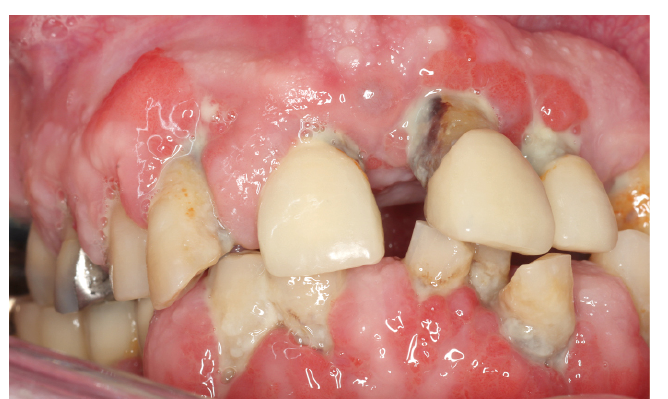

Der diabetische Patient Abb. 4

Abb. 4: Bei diesem 70-Jährigen mit Diabetes und arterieller Hypertonie kam es im langjährigen Verlauf zu einer vollständigen Vernachlässigung der Mundgesundheit. Dies zeigt sich in massiven oralen Erkrankungsausprägungen. Der Patient gab an, dass er die Zahnklinik aufgesucht habe, weil sein Nachbar ein Bonusheft hat und der Patient auch gern eines hätte. Somit veranlasste nicht die desolate Mundgesundheitssituation den Zahnarztbesuch des Patienten.